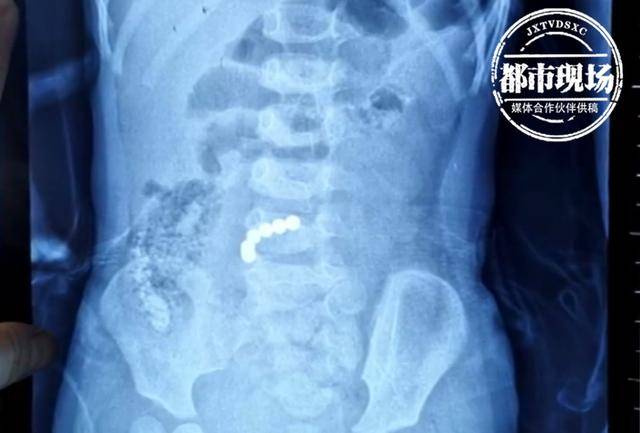

又是磁力珠!2岁女孩频频腹痛,医生一查发现肠子已经穿孔